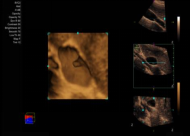

fourSight 4D technology 四维成像功能

‒ 实时三维成像

‒ 适用于腔内容积探头 8VC3 和 腹部容积探头 9VE3

‒ 提供多种高级四维成像功能:

多层断层成像、厚层断层成像和曲线任意多平面成像模式